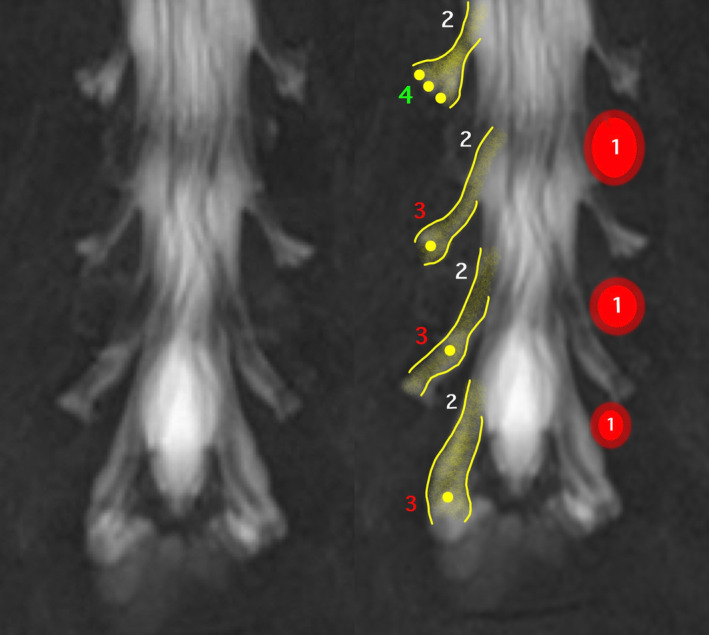

Discussion: Percutaneous procedure targeting the DRG for the treatment of chronic pain requires preoperative planning independent to the study of the etiology of pain. The DRG should be typified using magnetic resonance imaging. We propose a preoperative evaluation scale based on four specific items: A-position in the vertebral canal, B-position of the DRG within the foramen, C-number of ganglia in the root, and D-ratio (proportion) of foramen/DRG.

Abstract Image